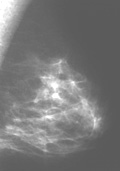

En la mamografía, hay dos signos principales de cáncer: calcificaciones y/o presencia de una masa. Las calcificaciones (depósitos de compuestos de calcio en la mama) aparecen como manchas blancas en una mamografía y ocurren en dos formas, microcalcificaciones y macrocalcificaciones. Las macrocalcificaciones tienden a ser grandes y de aspecto tosco y están asociadas con el envejecimiento. Son comunes en mujeres mayores de 50 años y están presentes en un pequeño porcentaje de mujeres más jóvenes. Las macrocalcificaciones no suelen estar asociadas con el cáncer. Las microcalcificaciones son más pequeñas y se consideran un signo de posible malignidad, incluso sin una masa visible.El radiólogo debe interpretar las características de la masa para determinar la posibilidad de cáncer y ordenará pruebas diagnósticas y posiblemente una biopsia.2

La imagen de la izquierda muestra la mamografía de una mama normal, mientras que la imagen de la derecha muestra una mamografía con una anomalía detectada (indicada por las flechas rojas). Haga clic en las imágnes para visitar su fuente, el Centro de Senos de la Universidad de St. Louis.